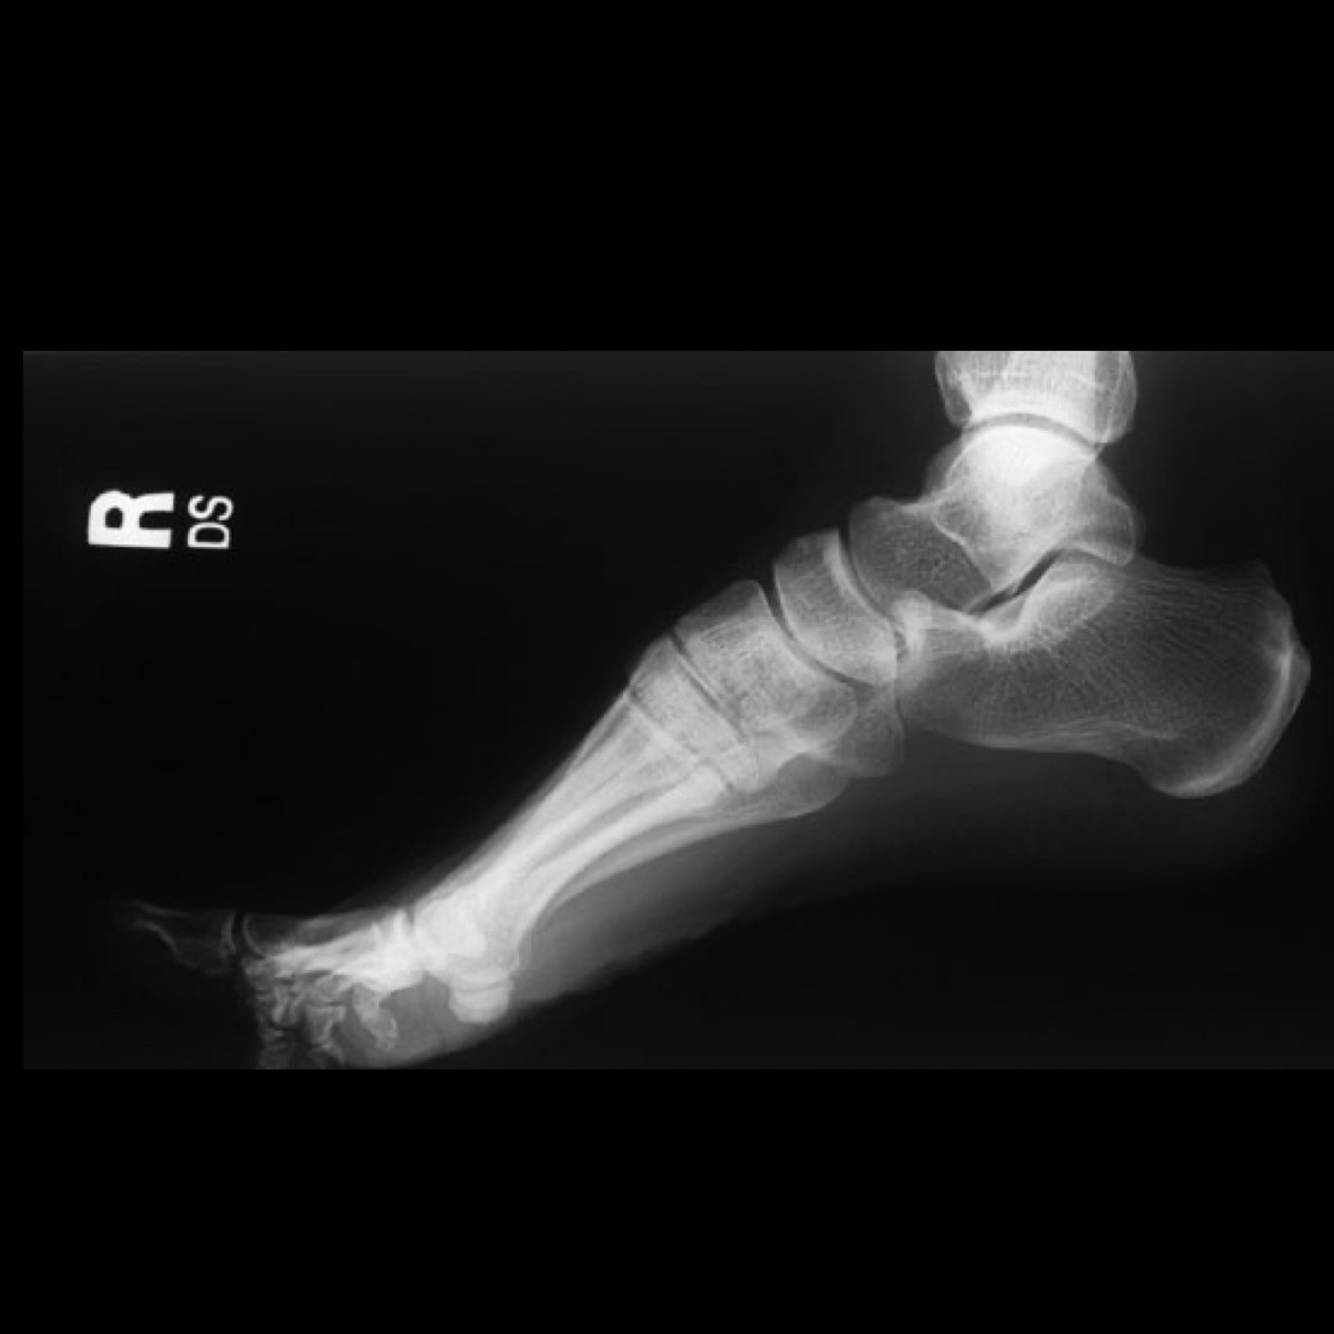

Quelle vue?

Évaluation de?

A

Projection latérale

Évaluation de:

• Arrière-pied et mi-pied • Sinus du tarse

• Angle de Boehler